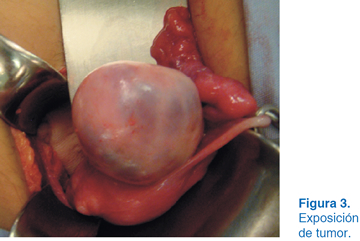

A los dos años del evento quirúrgico en el USG se apreció una tumoración en el ovario izquierdo con dimensiones de 10 x 12 cm (Figura 1). Se solicitó tomografía axial computarizada (TAC), observándose tumoración con densidades mixtas con diagnóstico probable de teratoma (Figura 2). Se optó por laparotomía exploradora donde se identificó el útero y se apreció tumoración dependiente de ovario izquierdo (Figura 3). Se realizó planeación de incisión (Figura 4), posteriormente tumorectomía (Figura 5) y salvamento de tejido ovárico (Figura 6). El reporte transoperatorio mostró teratoma monofásico con bordes libres de tumor.